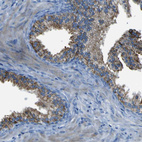

Immunohistochemistry analysis in human liver and tonsil tissues using HPA011964 antibody. Corresponding ACSL1 RNA-seq data are presented for the same tissues.